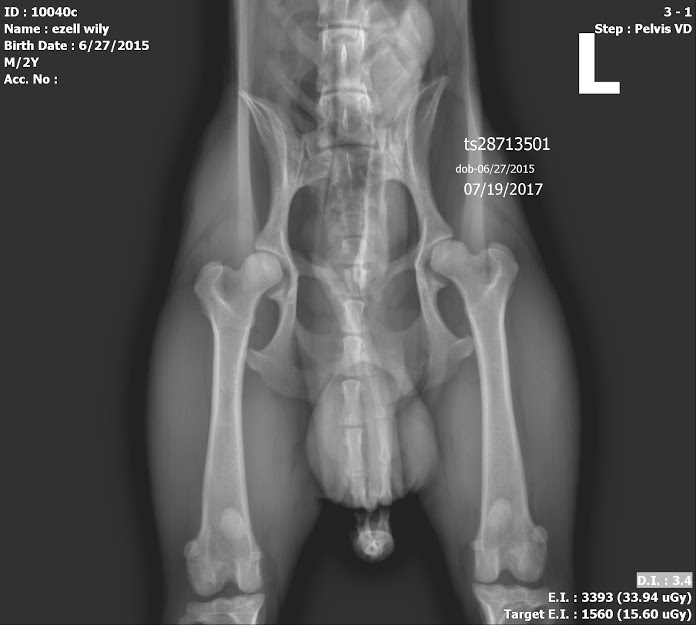

Due to some of the Cavalier King Charles Spaniel’s genetics and geriatric needs, you will find this breed has some of the more expensive rates on the market. The younger you decide to insure, your rates will be lower. When Willy was a young tyke, I looked into insuring him. I was quoted $50-$100 per month depending how much out of pocket I was willing to cover. I knew there would be puppy shots and a few tests that first year, but aside from that, I knew I could probably set aside $300 for him and barely touch it. Instead, I continued my search on a healthy, holistic approach to my Pet’s Care. A lot of what I do will be written in this blog forum. I treat my dogs similarly to how I treat my family and, especially, myself. Both warm-blooded mammals, there are some essentials that we all need to maintain a healthy life. Personally, outside of an Exam for a Certification two years ago, I haven’t seen a Doctor in about 7 years. I hope to maintain my health for a very long time! (And, by the way, I use a Cooperative for my Health needs (vs. Insurance). Getting in FRONT of the problems helps…but then, there’s always those once in a great while EMERGENCIES.